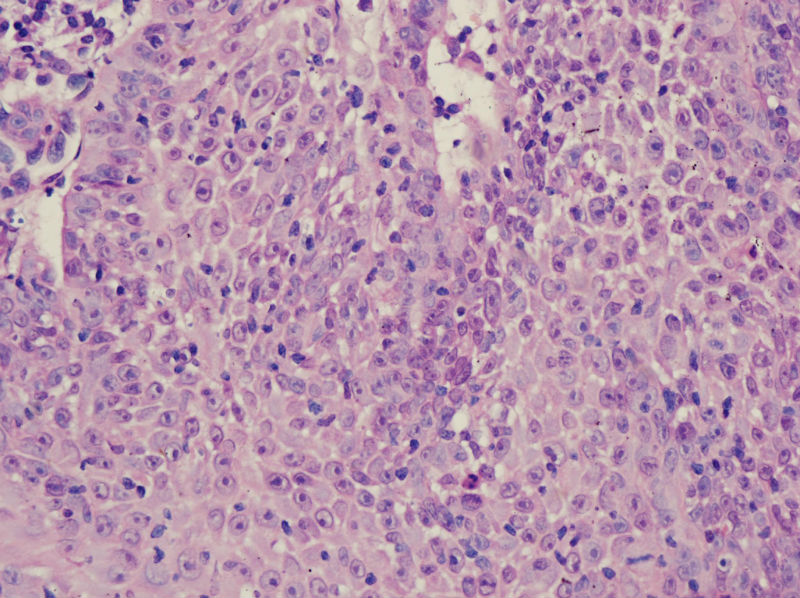

男,45岁,上唇菜花样肿物,请老师指教

图2